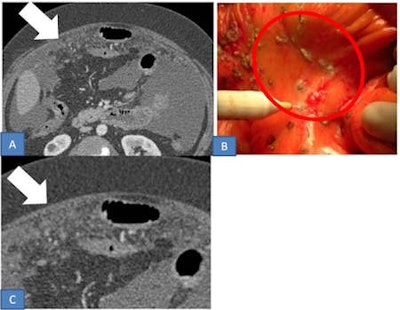

Ciolina wrote that peritoneal carcinosis is characterized by the presence of neoplastic implants with different morphological features and distribution in the peritoneal cavity. Radiologists must evaluate both morphology and localization. Solid, cystic, and mixed implants can present with different patterns that depict typical aspects of peritoneal carcinomatosis.

The micronodular pattern is characterized by the presence of tiny 1- to 5-mm milky spots of peritoneal implants diffusely involving the tunica serosa and subserosal fat. The greater omentum, lesser omentum, and mesentery are typically involved. Conversely, the nodular pattern is characterized by the presence of nodular implants larger than 5 mm diffusely involving the tunica serosa and subserosal fat. Nodules may have an oval shape with rounded contours or a star shape appearance with spiculated margins providing a stellate pattern, she pointed out.